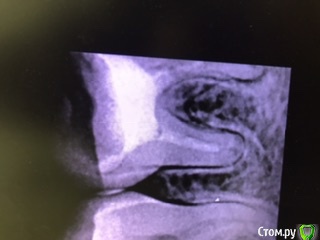

ho4u-vra4a Опубликовано 23 марта, 2020 Поделиться Опубликовано 23 марта, 2020 здравствуйте! обращаюсь к специалистам! пишу своим непрофессиональным языком, не судите строго.6 дней назад обратилась на перелечивание каналов с гранулемой ( или что это точно - я не знаю).46 зуб. мне установили коффердам, вскрыли старую пломбу, сверлили разными приборами, прочищали каналы, промывали хлоргексидином и гипохлоритом.весь процесс мучения длился полтора часа. в итоге мне запломбировали каналы с кальцием. поставили внутрь временную пломбу, а сверху еще закрыли постоянной. сделали рентген и отпустили домой. начинала я всю эту процедуру без анестезии, но в процессе все-таки попросила сделать её, так как было больно. и после того, как мне установили световую пломбу у меня уже начали боли в зубе усиливаться, а когда отошла заморозка - боли были невыносимые. врач сказала, что будет болеть, посоветовала пить ибупрофен.но я не ожидала, что боли будут настолько острые. к слову, мне не помогали ни ибупрофен, ни найз. я протерпела несколько дней, т.к врач не работала пару дней, и потом поехала к врачу снова. на мою просьбу сделать рентген - мне сказали, что я там все равно ничего не увижу. ок. они вскрыли мою световую пломбу, убрали все из зуба, включая пасту с кальцием, снова промыли все хлоргексидином, поставили туда внутрь так же хлоргексид и метронидазол. закрыли временной пломбой. боль во время данной процедуры прошла, но затем через несколько часов появилась снова. на следующий день я созвонилась с врачом, она сказала, что тогда придется пить антибиотики, т.к. уже началось воспаление и мой зуб "не прошел на герметичность". от предложенных антибиотиков я отказалась, т.к. у меня на них сильная аллергия. но указала, на какие группы антибиотиков у меня нет аллергии. врач сказала, что подумает и пригласила снова на осмотр на следующий день. в тот же день я открыла для себя кеторол, который помог заглушить острую боль. но появилось чувство распирания и как будто мне кололи в кость чем-то. на следующий день ( то есть уже сегодня) меня опять осмотрели, опять промыли каналы, опять поставили временную пломбу. через два часа я стала пить теплый ромашковый чай, и от него у меня снова острая боль. что мне делать? какие могут быть ошибки или может быть проблема в моем зубе и иммунитете? почему болит постоянно зуб, если причина боли должна уходить? прикрепляю рентген до и рентген после первого лечения. также есть КТ до перелечивания, вдруг кто-то заинтересуется. спасибо! 1 Ссылка на комментарий